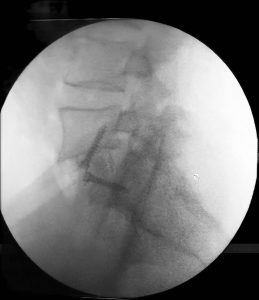

الاربعاء 16-10-2024 أجرى فريق طبي في قسم جراحة الاعصاب /مستشفى الأمير حمزة بالتعاون مع جراحة الأوعية الدموية عملية نوعية و الاولى في مستشفيات وزارة الصحة لمريض يعاني من ازاحة من الدرجة الثانية بين الفقرات القطنية الخامسة و العجزية الاولى مع تضيق و ضغط على الاعصاب ، حيث تم إجراء عملية دمج للفقرات و تعديل الإزاحة و توسيع مخارج الاعصاب من الامام من خلال البطن (النهج الامامي ).

يساعد هذا التدخل الجراحي على تجنب تشريح العضلات والهياكل العظمية والتدخل عبر الأعصاب الذي يمكن للمرء أن يجده في حال تم التدخل عن طريق الظهر.

تتمثل مزايا هذا التدخل الجراحي في أنه يسمح بعرض العمود الفقري بشكل ممتاز، مما يتيح إدخال عناصر أكبر حجماً، مثل الأقراص الاصطناعية أو أقفاص دمج الفقرات التي تكون مساحتها أكبر بكثير من تلك التي يتم إدخالها من الجهة الخلفية. ويكون تعافي المريض سريعاً جداً، مع إمكانية التخريج من المستشفى بعد يومين من التدخل الجراحي.